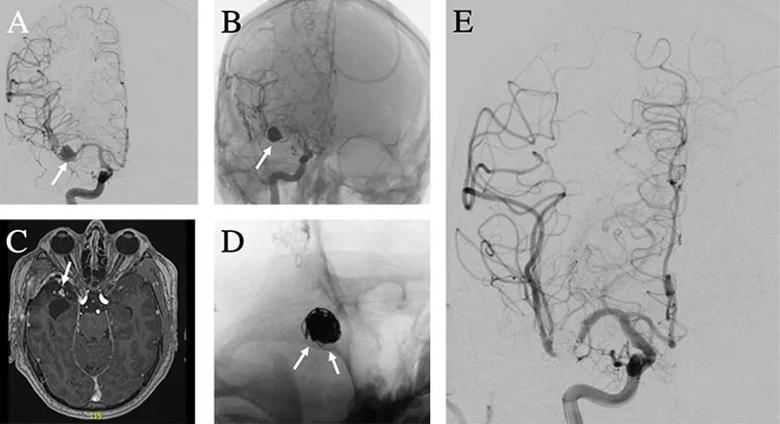

All aneurysms demonstrated complete occlusion at long-term angiographic follow-up, and no patients developed new complications or neurological deficits. Representative imaging studies from one of the patients are presented in the figure.

Figure. Case illustration of flow-diverting stent use in mycotic aneurysm. (A) A right middle cerebral artery mycotic aneurysm (arrow) was found on a workup of intracerebral hemorrhage in a patient with infective endocarditis. (B) The aneurysm was successfully treated with balloon-assisted coil embolization (arrow) without residual flow into the aneurysm. (C) Magnetic resonance angiography three months later demonstrated residual contrast enhancement at the neck and in the aneurysm lumen suggestive of coil compaction and aneurysmal recurrence (arrow). (D) A flow-diverting stent was successfully placed across the aneurysm neck (arrows). (E) Follow-up angiography at 11 months demonstrated no residual flow into the aneurysm.